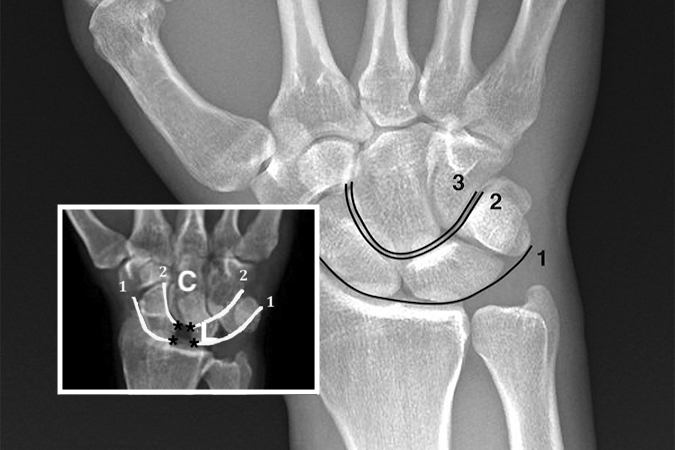

• Injuries disrupt Gilula's lines. Normal Gilula's lines superimposed on a neutral deviation PA wrist x-ray. Arc 1 is a smooth arcing line paralleling the proximal articular surfaces of the triquetrum, lunate, and scaphoid. Arc 2 parallels the distal concave surfaces of the triquetrum, lunate, and scaphoid. Arc 3 parallels the smooth curved surface of the proximal hamate and capitate.

Injuries disrupt Gilula's lines (Insert). Normal Gilula's lines superimposed on a neutral deviation PA wrist x-ray. Arc 1 is a smooth arcing line paralleling the proximal articular surfaces of the triquetrum, lunate, and scaphoid. Arc 2 parallels the distal concave surfaces of the triquetrum, lunate, and scaphoid. Arc 3 parallels the smooth curved surface of the proximal hamate and capitate.